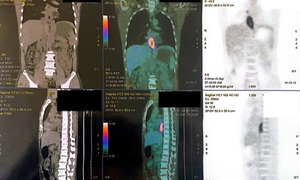

Đi khám vì viêm dạ dày - thực quản trào ngược, người đàn ông bất ngờ phát hiện chỉ số CEA tăng rất cao, từ đó lần ra ung thư phổi hiếm gặp.